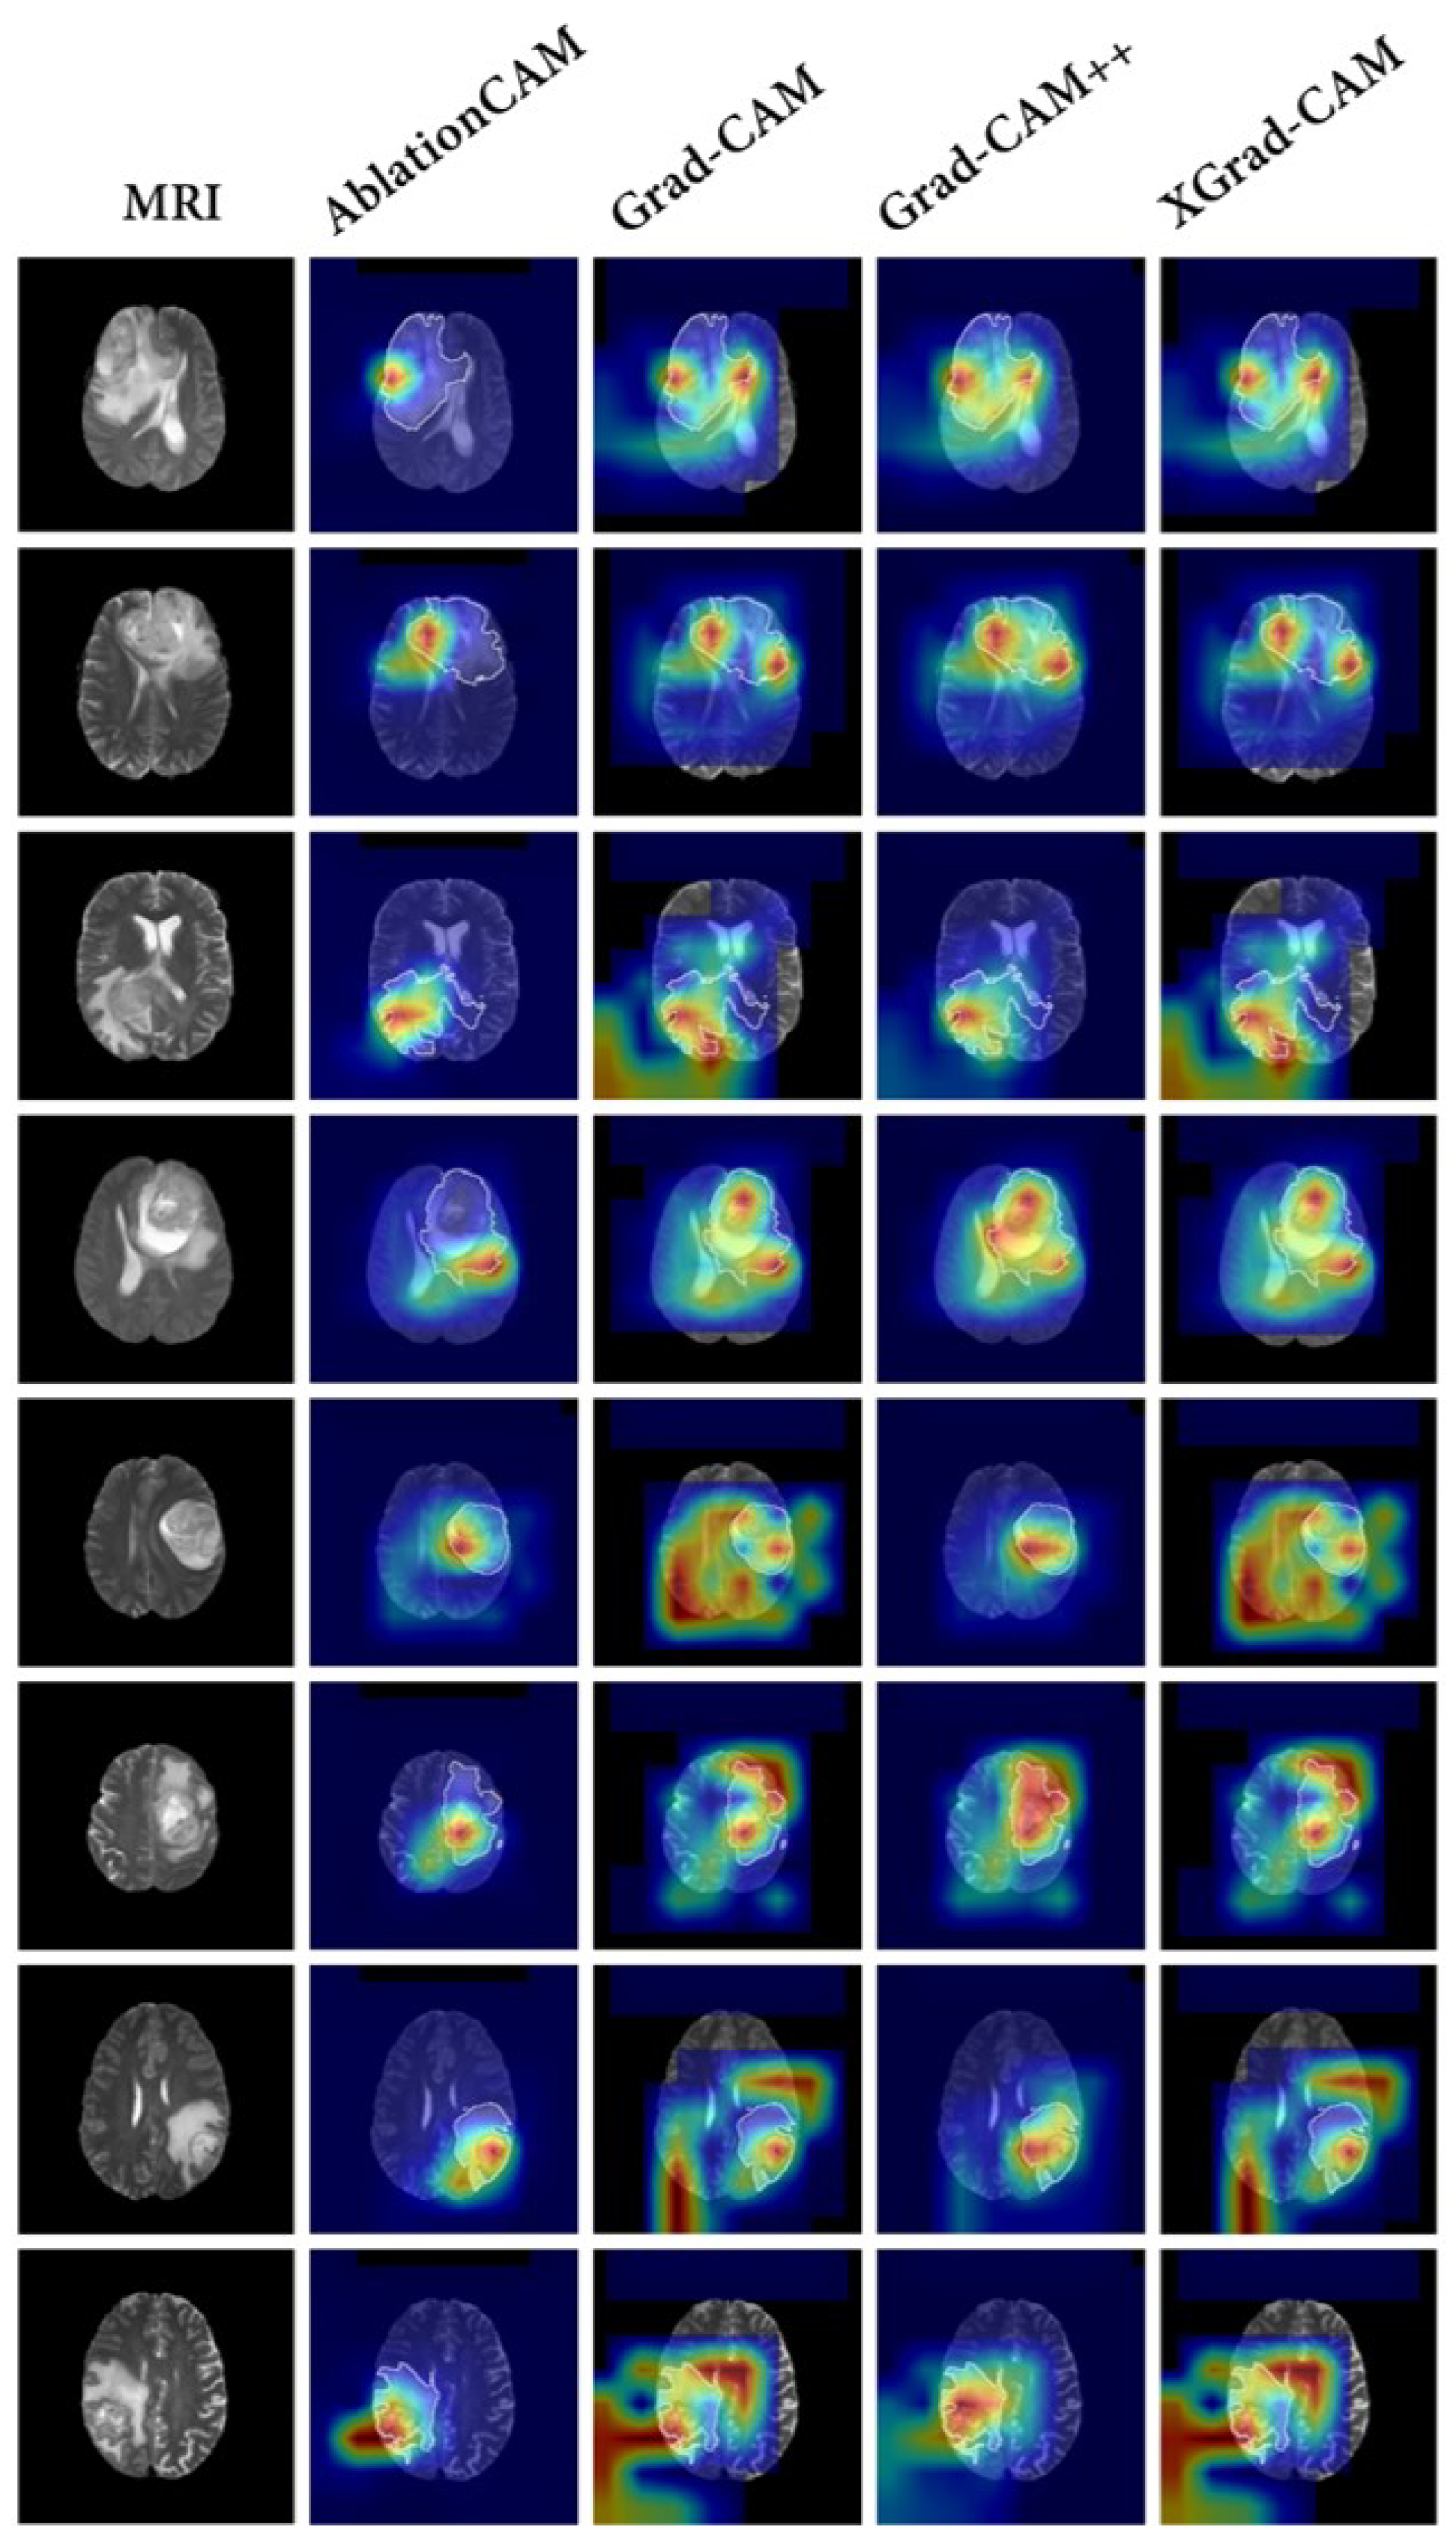

4.7. Comparison with Baseline Visualization Methods

To compare our proposed interpretable method with conventional methods, we conducted a comparison using the baseline model SEResNet, which exhibited the best classification performance. We selected AblationCAM [35], Grad-CAM [21], Grad-CAM++ [36], and XGrad-CAM [37] as the baseline visualization methods to explain the model’s decision-making process. The results are shown in Figure 6.

In general, the results of the baseline models exhibited a diffuse distribution pattern. Among all of the baseline methods, AblationCAM [35] performed the best and was able to focus on the tumor region more accurately. However, it still exhibited some false attention, such as focusing on the black background. This false attention is often problematic in interpretation methods, since the model does not utilize any information from the black background that would be beneficial for classification.

In contrast, the proposed CSF demonstrates the search process of key subregions, as shown in Figure 7. After training the segmentation results of our model using the proposed strategy, the segmented subregions are reduced to the key subregions.

Our method provides clear and specific visualization of the key subregions, which is significantly better than the vague explanations provided by other methods. It is important to note that, due to the causal aspect of our model design, these subregions inherently contain the complete information required for making predictions.

Furthermore, the shrinkage strategy employed in our model helps to focus on the correct areas and reduce misclassified attention. This contributes to the overall improvement of classification performance.

Figure 6. The results of baseline visualization methods. In the traditional methods, AblationCAM [35], Grad-CAM [21], Grad-CAM++ [36], and XGrad-CAM [37] are used to explain the trained SEResNet [29]. Specifically, The first column shows the T2 fluid attenuated inversion recovery (FLAIR) MRI. Columns 2–5 show the visual explanations for AblationCAM [35], Grad-CAM [21], Grad-CAM++ [36], and XGrad-CAM [37], respectively. Different colors in a heatmap represent varying levels of attention. In these examples, the transition from red to blue indicates a descending order of attention.

Figure 7. The results of our framework (CSF). This result shows the decision-making process of the model, that is, how the model shrinks to key subregions. Specifically, the first column shows the T2 fluid attenuated inversion recovery (FLAIR) MRI. Columns 2–4 show the ground truth of tumor segmentation (Green), the segmentation results of the model (Blue), and the shrinkage results of the model (Red), respectively.